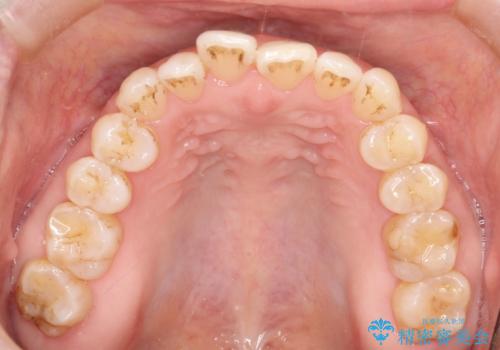

前歯の隙間 インビザラインによる目立たない成人矯正

- 前歯の隙間を気にされて来院されました。

インビザラインにて、目立たずに矯正治療を行うこととしました。

歯と歯の間にある隙間を閉じるのは、インビザラインでもしっかり治療できます。